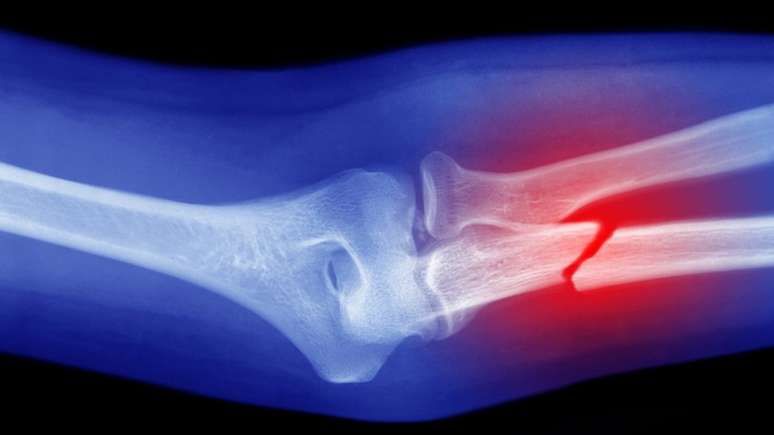

Como o próprio nome indica, os ligamentos conectam e permitem a movimentação do local onde dois ossos se encontram. Na ilustração, eles são essas estruturas brancas no meio do joelho, que conectam o fêmur (acima) com a tíbia (abaixo)

A fratura ocorre quando o osso se quebra